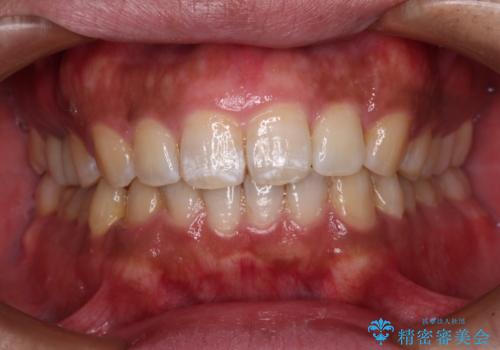

破折して抜歯が必要となった歯の後ろの歯は、根管治療が必要な状態であったので、根管治療を行い、矯正治療後にインプラント部の補綴治療と同時にセラミッククラウンを装着しました。

矯正治療以外に費用負担がかかることになりましたが、気になるところ全てを処置することができ、患者様には大変満足していただきました。